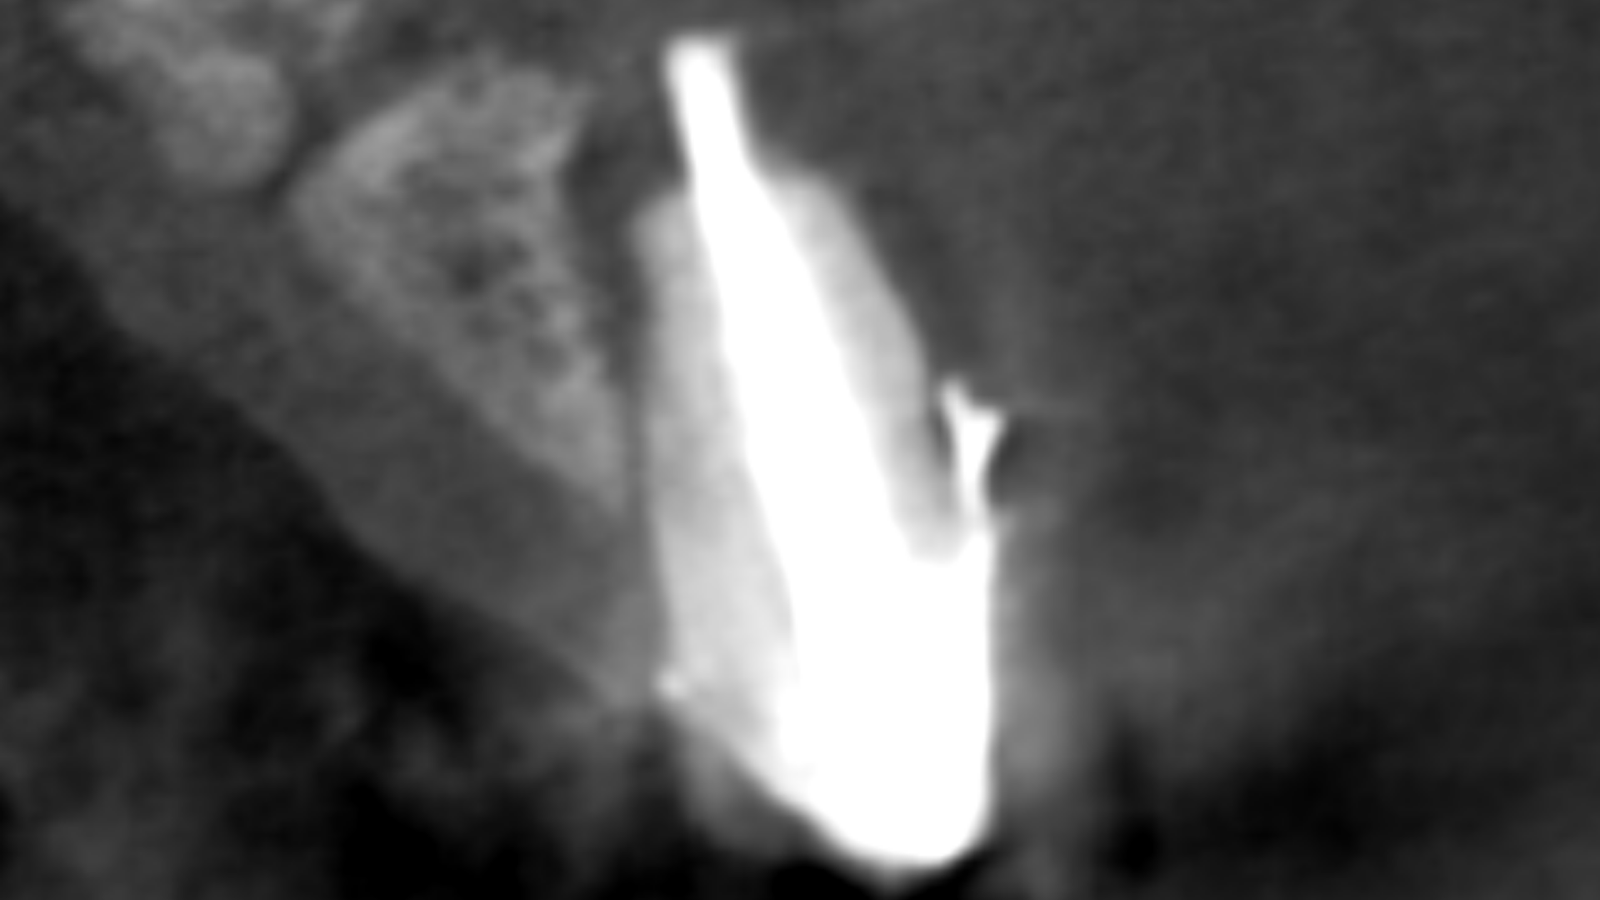

Un patient se présente avec une incisive centrale droite (11) dévitalisée, ainsi que l’incisive latérale homolatérale (12), également dévitalisée.

Ces deux dents présentent des images de résorption osseuse discrète en rapport avec la dévitalisation, avec un kyste de 12 mm au niveau de la 12.

11 : extraction avec greffe osseuse (mélange os bovin + os du patient prélevé au niveau du ramus), le tout recouvert d’une membrane et fixé avec des pins.

12 : résection de la partie apicale avec un remplissage rétrograde au MTA.

À 6 mois : mise en place d’un implant.

3 mois après : mise en place d’une couronne vissée en zircone.